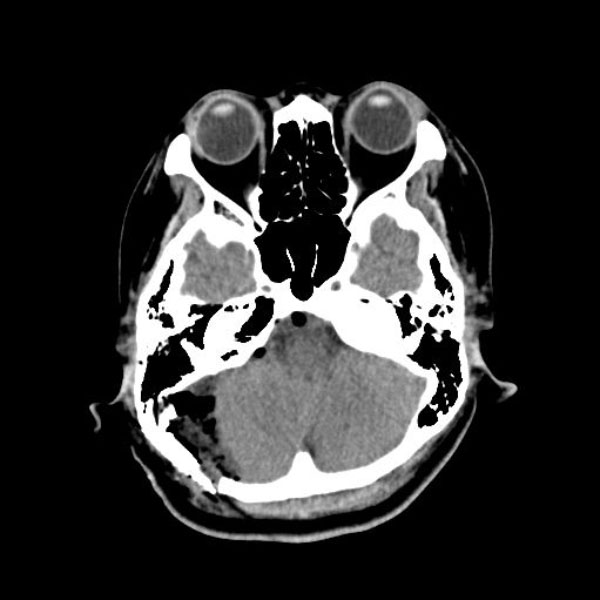

症例 '26年4月

No.

588

手術医師

手術年月

年齢

病名

術式

手術前

減圧前

減圧後

手術後

京都府の病院

'26年4月

40代

右三叉神経痛

(顔面の痛みをとること)

術後血管撮影